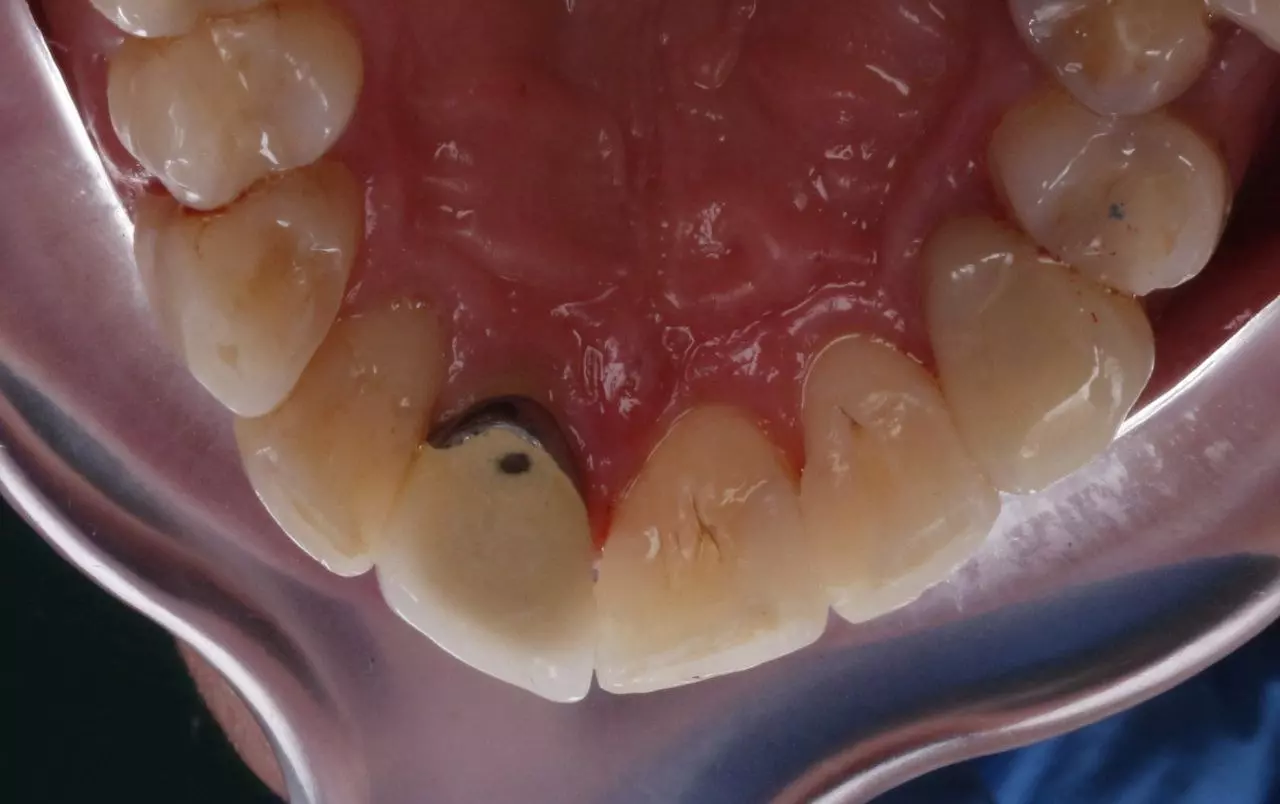

Художня реставрація 21.22.